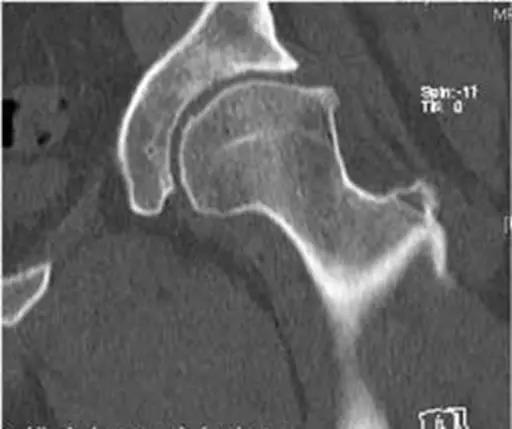

CT表现

- 扫描部位自髋臼到小转子。

- 以股骨颈轴线为旋转中心轴,所谓股骨颈轴线。

- 根据两个骨盆基点来定:股骨头中心点和股骨颈最狭窄部。

- CT表现与X线平片相同。

- 能更清晰显示细微骨质结构改变:髋臼边缘的骨赘、股骨颈疝窝、关节面下囊变等细节。

凸轮撞击型FAI▼

- 股骨头颈联合处前上缘骨性突起。

- 非圆形的股骨头。

- 股骨头颈联合处前缘骨性突起、骨质硬化,α角增大。

钳夹撞击型FAI▼

- 横断面显示髋臼后倾:正常髋臼连线与水平线呈钝角;呈锐角,提示髋臼后倾。